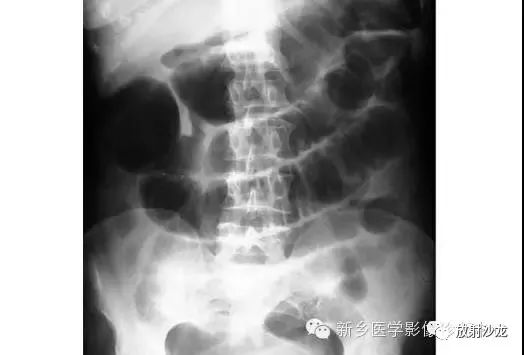

上张X线片在小肠靠近横结肠处出现几圈膨大后合并狭窄。术中发现该患者由于肠系膜动脉栓塞致小肠肠襻坏疽。

病人出现腹部不适的明显迹象。大肠梗阻在腹部平片上会表现为什么呢?

结肠扩张是由于粪便嵌塞。大肠可通过结肠袋来识别,并且其从升结肠延续至乙状结肠。由于排泄物挤压致粪便和气体积聚使直肠存留少量气体。这可通过肛门镜检或直肠指诊来确认。